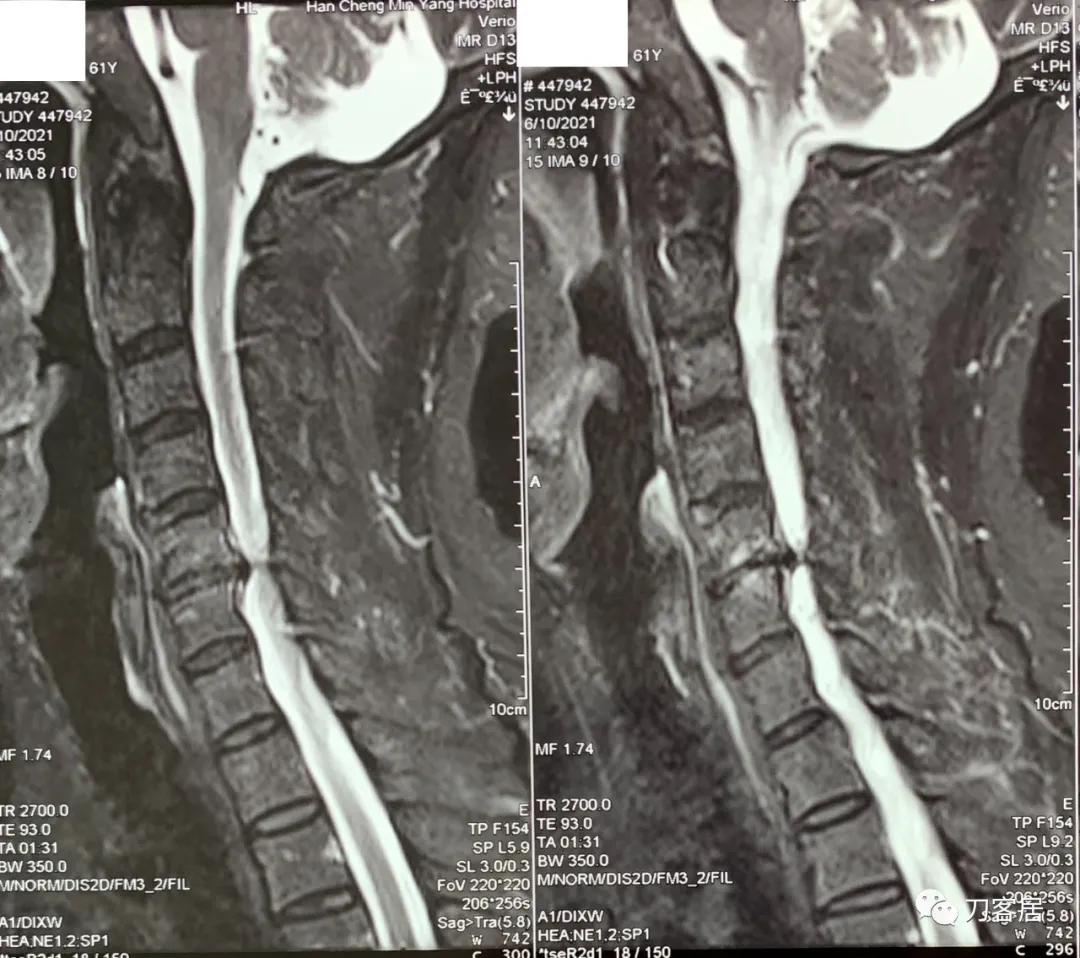

自带颈椎MRI显示颈5-6椎间盘突出,黄韧带肥厚,椎管狭窄,脊髓受压较重,但目前症状较轻,无明确神经损伤表现,暂不考虑手术。

诊断:颈椎间盘突出,黄韧带肥厚,椎管狭窄。

图3. 20210610韩城医院颈椎MRI矢状面T1相。

图4. 20210610韩城医院颈椎MRI横截面颈5-6椎间隙T2相,提示颈5-6椎间盘突出及椎管狭窄并不严重。